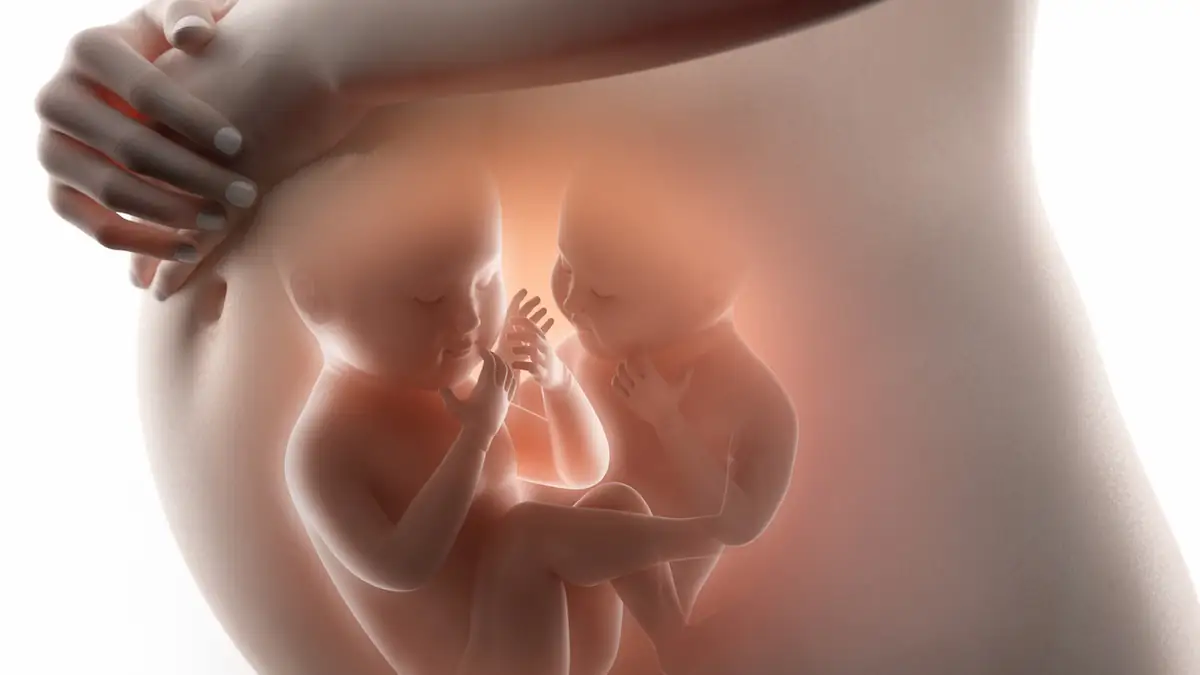

Eine dieser freiwilligen Leihmütter ist Courtney Williams, die aktuell auch als solche schwanger ist. Allerdings stellte sich heraus, dass sie nicht mit einem Baby schwanger ist, sondern mit Zwillingen. Während es regelmäßig vorkommt, dass entgegen der Erwartungen zwei Kinder unterwegs sind, sind die anderen Details des Falls alles andere als gewöhnlich. Denn wie Untersuchungen ergaben, sind die beiden Zwillinge überhaupt keine Geschwister.

Eines der Babys entstand aus der befruchteten Eizelle, die Courtney Williams eingesetzt wurde und ist folglich das Kind der sogenannten Wunscheltern. Das andere jedoch ist von Courtney und ihrem Mann; es muss kurz nach der künstlichen Befruchtung gezeugt worden sein. Rein rechtlich ist die Lage damit klar, zumal man mit Tests schnell herausfinden kann, welcher Zwilling zu welchen Eltern gehört. Medizinisch ist der Fall allerdings außergewöhnlich.